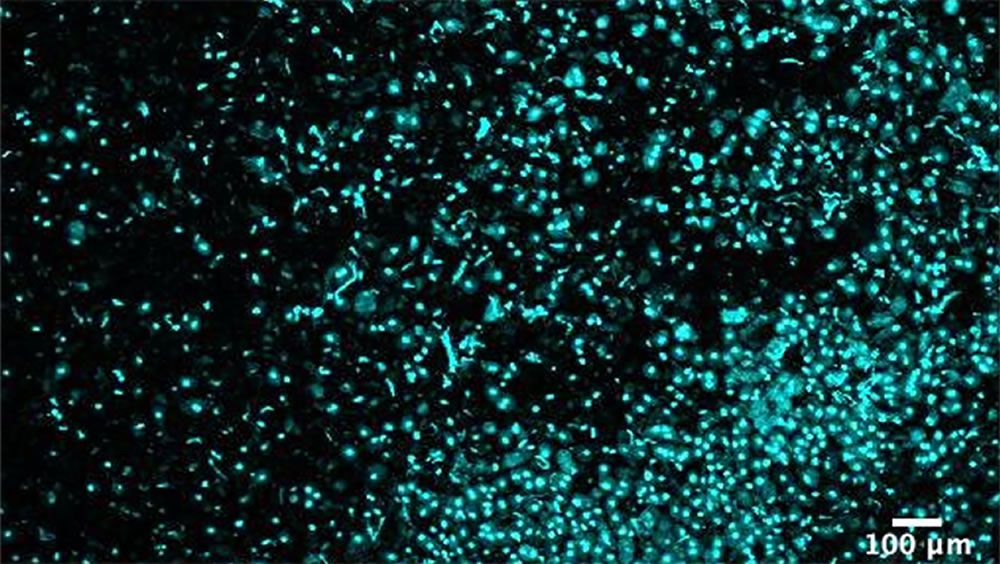

La tecnología implica el uso de campos eléctricos fluctuantes para separar suavemente las células y necesita tan solo cinco minutos, que es más rápido que los métodos existentes para disociar tejidos, como los que usan enzimas o técnicas mecánicas. Sorprendentemente, las células disociadas no solo son adecuadas para el análisis genético, sino que sobreviven al proceso relativamente ilesas y viables, lo que sugiere que el enfoque puede prestarse a varios enfoques de investigación que requieren una suspensión de una sola célula y luego un cultivo celular adicional.

"Existe una gran necesidad de una tecnología que permita la extracción de tejido del paciente y, en cuestión de minutos, dé como resultado células individuales sanas y viables de las que se pueda aislar el ARN", ha expresado Nikos Tapinos, otro investigador involucrado en el estudio. "Eso es exactamente lo que hace este nuevo proceso", ha sentenciado.